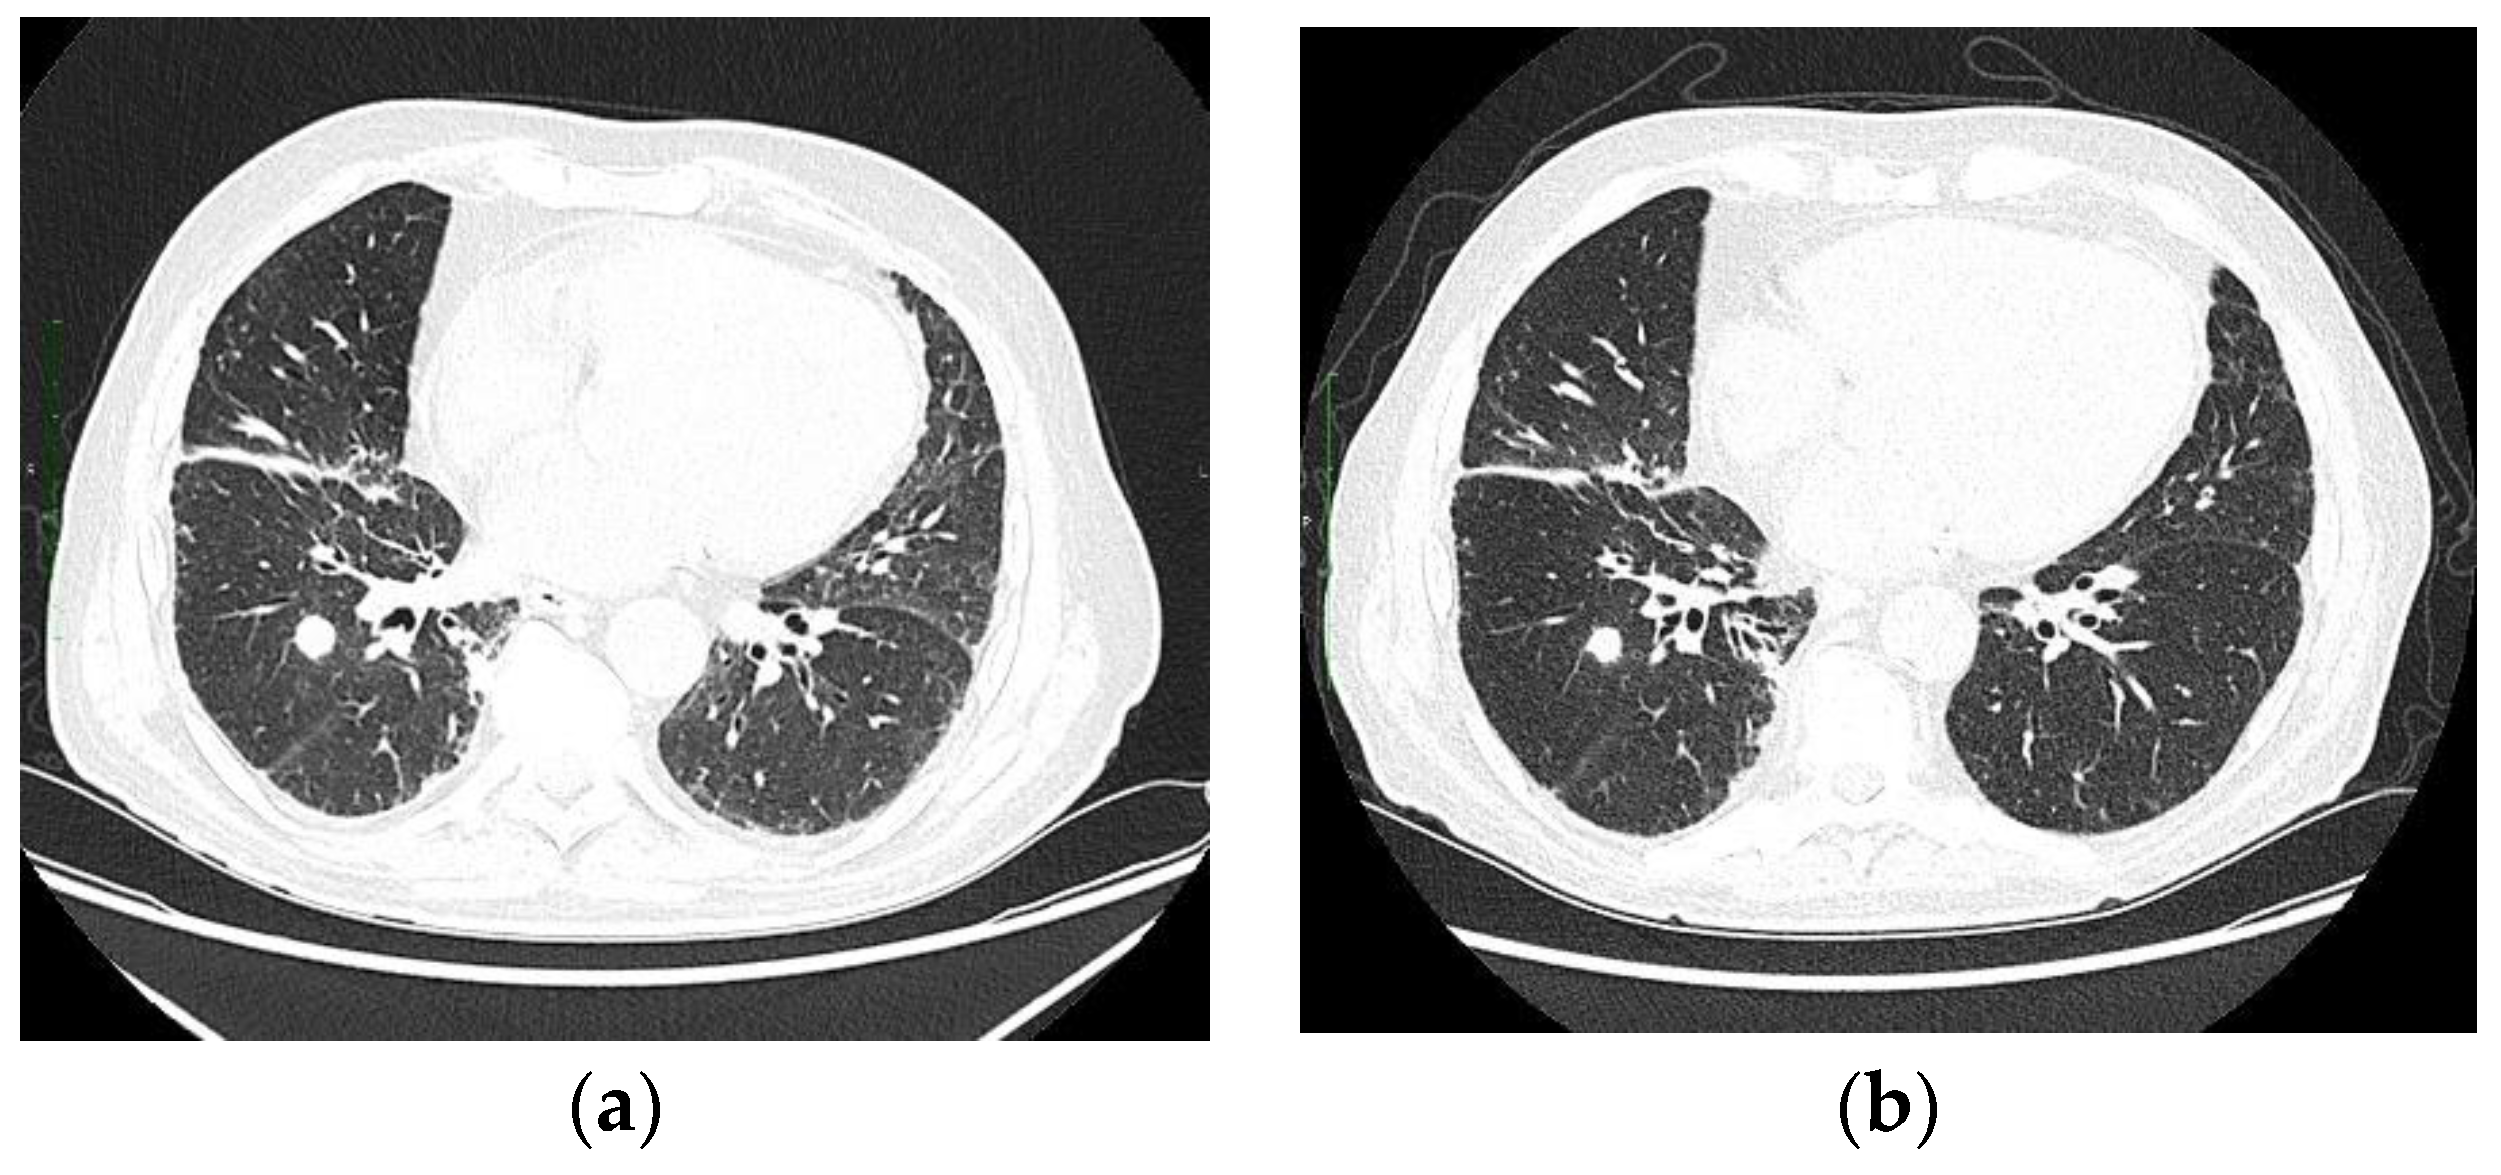

2. Case Description